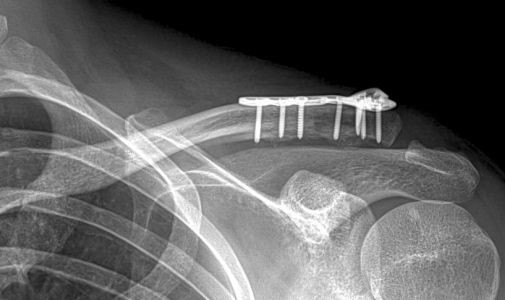

Eventuele operatie Slechts in bepaalde gevallen is er een reden voor een operatie. Een harde reden voor een operatie kan zijn dat een botstuk door de huid dreigt heen te gaan. Ook kan een sterk afwijkende stand een reden zijn voor een operatie. De nadelen van een operatie (ontsierend litteken, infectiekans, uitbreken van fixatiemateriaal) wegen echter vaak niet op tegen de voordelen (standscorrectie). Uw behandelend arts zal samen met u een afweging kunnen maken hoe dat in uw specifieke situatie is. Bij sleutelbeen breuken waarbij de breuk helemaal aan de zijkant ligt, zal er wel sneller naar een operatieve behandeling worden geneigd. Indien er voor een operatie wordt gekozen, zal er meestal gebruik worden gemaakt van een plaatje met schroeven.